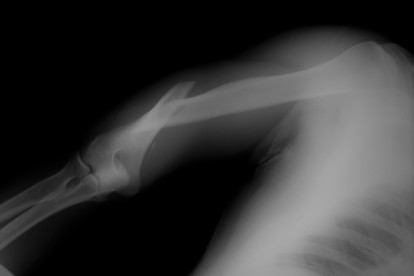

For older nursing home residents, broken bones can be life-changing, traumatic experiences, and they can take months or years to recover from. Older individuals have weaker, more brittle bones than younger people, making them easier to break and more difficult to heal.

Broken bones in nursing homes are almost always caused by falls. When a nursing home patient falls, the injuries can be extensive: arms, legs, hips, and pelvises can all break from a trip and fall in a nursing home. Some of the causes of falls in nursing homes include: